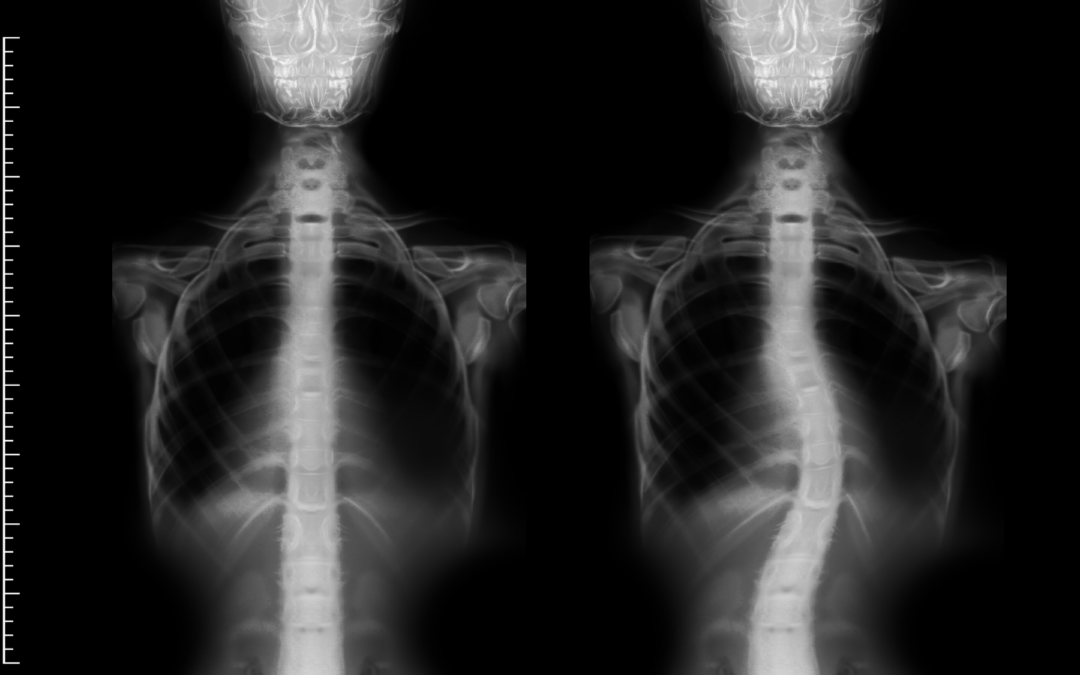

by 28177pwpadmin | Apr 15, 2026 | AMC, Arthrogryposis, Cebrebral Palsy, Featured, NF1, Prader-Willi, Scoliosis

Prader–Willi Syndrome (PWS) is a complex genetic condition caused by abnormalities in chromosome 15, leading to low muscle tone (hypotonia), growth hormone deficiency, and unique metabolic and behavioral challenges. While most discussions focus on appetite and...